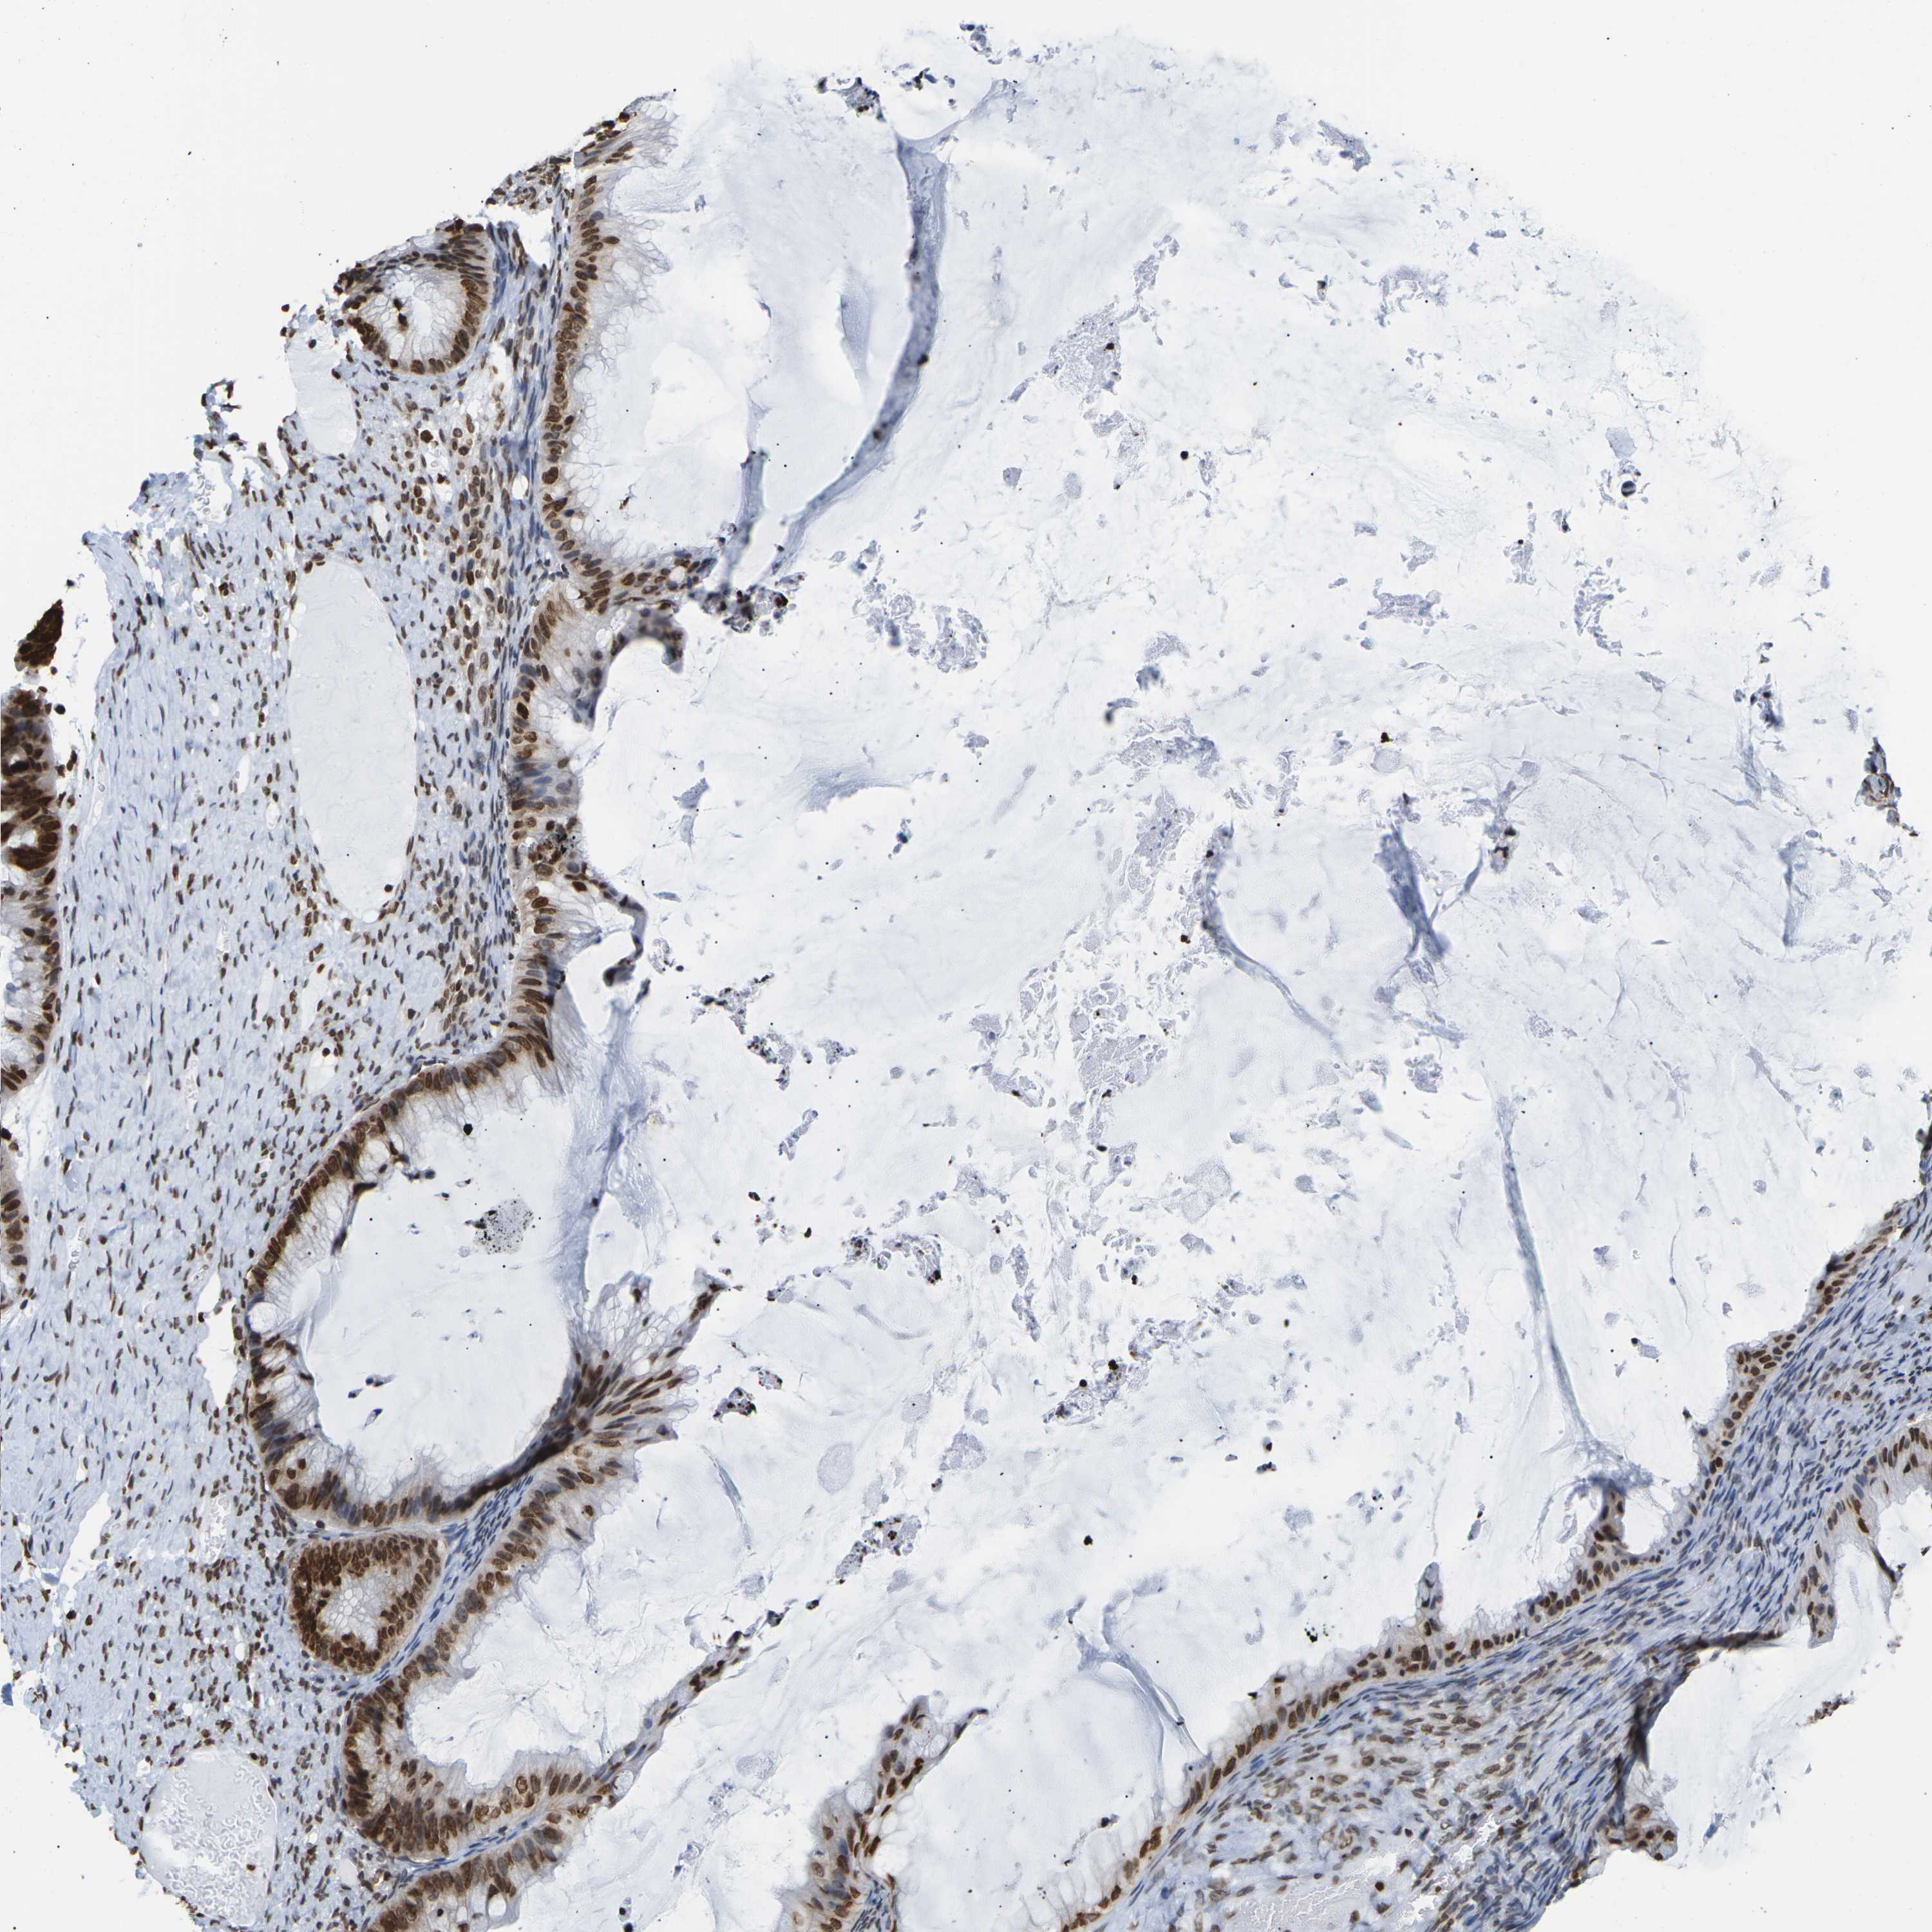

OVARIAN CANCER - Protein expressioni

A mouse-over function shows sample information and annotation data. Click on an image to view it in a full screen mode. Samples can be filtered based on level of antibody staining by selecting one or several of the following categories: high, medium, low and not detected. The assay and annotation is described here.

Note that samples used for immunohistochemistry by the Human Protein Atlas do not correspond to samples in the TCGA dataset.

Antibody stainingi

Antibody staining in the annotated cell types in the current human tissue is reported as not detected, low, medium, or high, based on conventional immunohistochemistry profiling in selected tissues. This score is based on the combination of the staining intensity and fraction of stained cells.

Each image is clickable and will lead to virtual microscopy that enables deeper exploration of all samples and also displays staining intensity scores, fraction scores and subcellular localization as well as patient and tissue information for each sample.

Antibody HPA041189

Antibody CAB011483

Staining

High

Medium

Low

Not detected

Intensity

Strong

Moderate

Weak

Negative

Quantity

>75%

75%-25%

<25%

None

Location

Nuclear

Cytoplasmic/membranous

Cytoplasmic/membranous,nuclear

Cystadenocarcinoma, serous, NOS

Carcinoma, endometroid

Cystadenocarcinoma, mucinous, NOS

Carcinoma, NOS